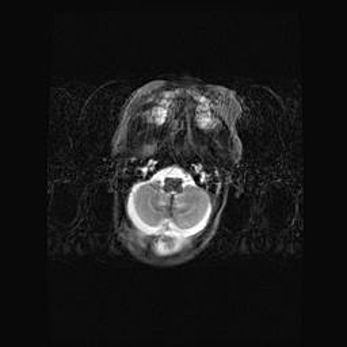

Подострая гематома правой гемисферы мозжечка.

Наружная гидроцефалия.

Возраст: 15 дней

Вес: 3100 г

Пол: женский

Окружность головы: 37 см

Срок гестации: 35-36 недель

При открытой наружной форме гидроцефалии у новорожденных расширяются и переполняются субарахноидные пространства.

Кровоизлияния в мозжечок имеют две клинико-анатомические формы: полушарные гематомы и кровоизлияния в червь.

К появлению этой патологии может привести: повреждения головного мозга, возникающие в результате асфиксии и гипоксии плода при беременности, или травмы во время родов. Редко гематома мозжечка может быть результатом первичной коагулопатии и сосудистой мальформации, диссеминированном внутрисосудистом свертывании, изоиммунной тромбоцитопении.